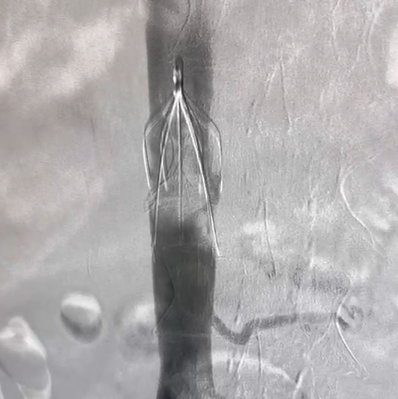

Vewatch®/海神盾™腔静脉滤器通过经股静脉或经颈静脉入路经皮置入,用于预防下腔静脉系统栓子脱落而引起的肺动脉栓塞(PE)。包括:1.已经发生PE或下腔静脉及髂、股、腘静脉血栓形成的患者有下述情况之一者:(1)存在抗凝治疗禁忌证者;(2)抗凝治疗过程中发生出血等并发症;(3)充分的抗凝治疗后仍复发PE和各种原因不能达到充分抗凝者。2.PE,同时存在下肢深静脉血栓形成者。3.髂、股静脉或下腔静脉内有游离漂浮血栓或大量血栓。4.诊断为易栓症且反复发生PE者。5.急性下肢深静脉血栓形成,欲行经导管溶栓和血栓清除者。